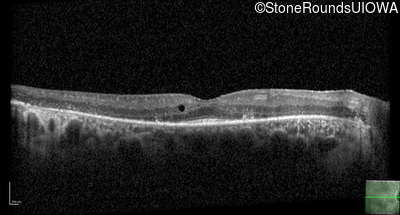

Optical Coherence Tomography - Left - 20/32

Exemplar / OCT Stack

OCT Stack